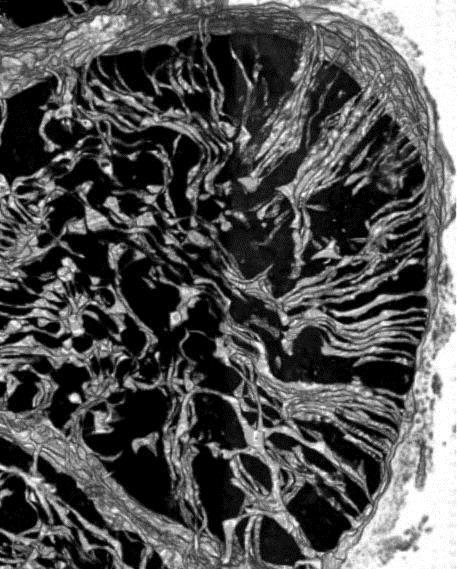

Newly released images revealing the 'bicycle spoke' structure of a heart cell may hold key clues to reducing damage from a heart attack.

Using a novel type of electron microscopy, Dr Kitmitto and team produced 3D images of a healthy heart cell at nanoscopic scale which shows part of their structure is arranged like spokes on a wheel.

These 'spokes', called T-tubules carry an electrical signal from the outside of the cell to the inside and are necessary for the coordinated transmission of the electrical impulse through the cell to enable the heart cells to contact and enable the heart to pump blood around the body.

But following a heart attack, the T-tubules are lost in many areas and the electrical signal cannot be carried properly through the cells. The remaining T-tubules also appear to fuse and clump together forming very large, but distorted, 'super-tubules'.

"The regular pattern of T-tubules - like spokes on a wheel - is really important because it means the whole heart cell can receive the same information and it can contract together.

"But following a heart attack that regular structure is lost, so some parts of the cell will get the signal and other parts won't.